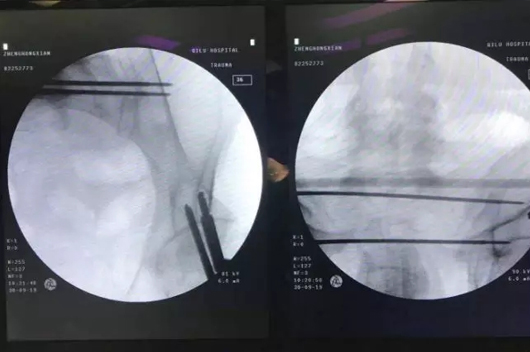

4.jpg

▲  术前及术中妄想

5.jpg

▲  导针及螺钉精准植入